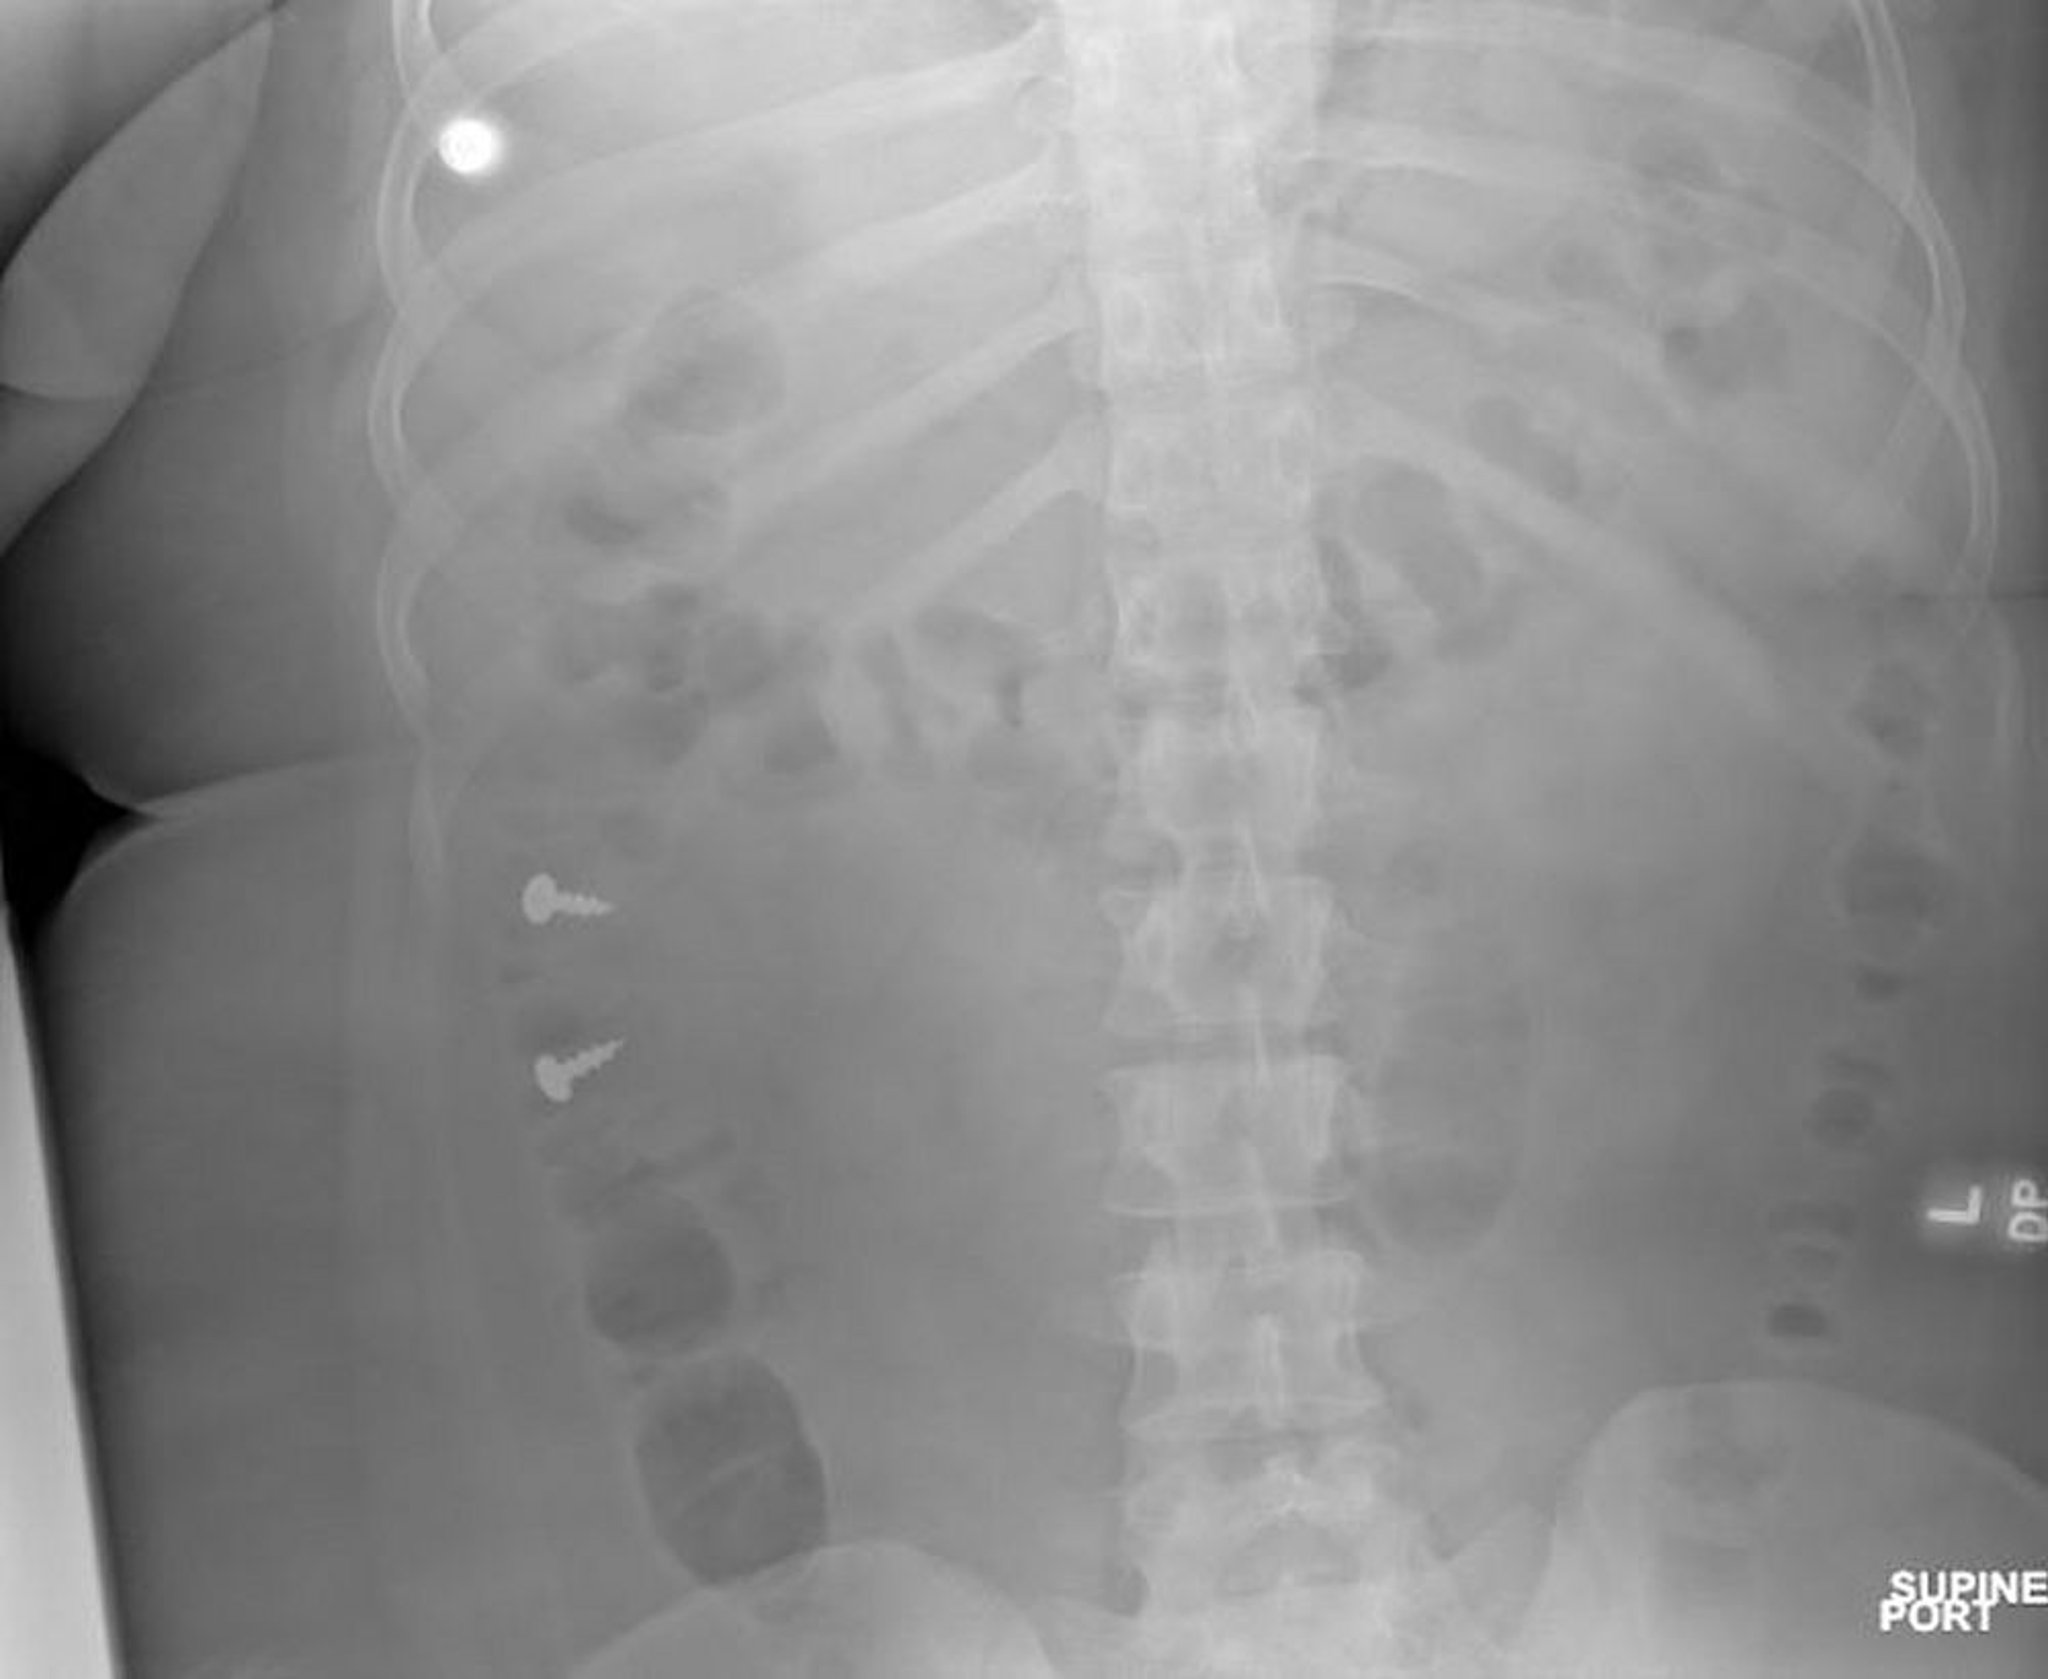

Vis dans le côlon (radiographie)

Image courtoisie de Zubair Malik, MD.